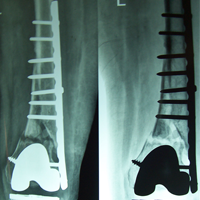

Case:14 Periprosthetic Fracture

60 years old patient with total knee replacement on left knee presented with open grade 1 injury. Debridement & slab given on emergency bases. Fixation with plate & screws done. Union was seen after 6 months.

Pre-Op AP

Pre-Op Lat.

Immdiate Post-op

1 and half months Post-op

2 and half months Post-op

3 and half months Post-op

4 and half months Lateral

6 Years Follow-Up